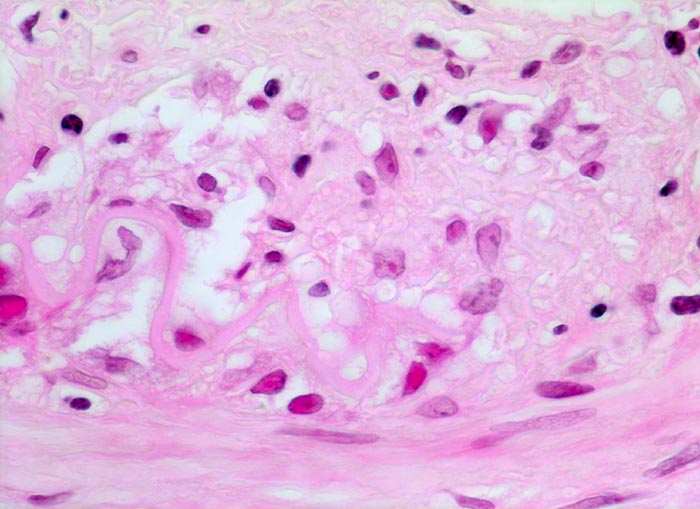

PathoPic – image database / PathoPic ID 4641 - Arteritis temporalis Horton (Riesenzellarteriitis)

Arteritis temporalis Horton (Riesenzellarteriitis)

An der Grenze zwischen Media und Intima (oben) Reste einer fragmentierten Lamina elastica interna. Lymphozytäres und Histiozytäres Infiltrat im Bereich der Media-Intima Grenze.

Riesenzellen sind nur bei zwei Drittel aller Fälle nachweisbar. Da die Läsionen meist segmental verteilt sind, sollte eine Biopsie idealerweise ein 4-5cm langes Arterienteilstück umfassen. Das Gewebe wird vollständig eingebettet und mit Stufenschnitten untersucht.